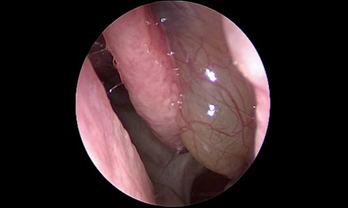

- Phát hiện sớm các trường hợp polyp mũi xoang, ung thư vòm họng qua nội soi.

Phẫu thuật nội soi chức năng xoang (Functional Endoscopic Sinus Surgery-FESS) giúp trả lại hệ thống xoang thông thoáng với kỹ thuật không đặt bấc mũi.

Công nghệ phẫu thuật nội soi hiện đại

- Phẫu thuật nội soi mũi xoang với hệ thống định vị trong lúc mổ (Navigation) cho phép bác sĩ tiếp cận trực tiếp đến các vùng mũi xoang bị viêm, gia tăng khả năng quan sát các mốc giải phẫu trong hốc mũi để đánh giá một cách chính xác các bệnh lý sâu trong hốc mũi.

- Trên cơ sở đó, bác sĩ có thể dễ dàng thao tác loại bỏ sạch các tác nhân gây viêm và mủ mà vẫn bảo tồn tối đa niêm mạc lành và hạn chế nạo bỏ niêm mạc triệt để, tối ưu lưu thông không khí trong hệ thống xoang.

- Hỗ trợ đắc lực cho các ca phẫu thuật xoang tại bệnh viện SIS Cần Thơ là hệ thống nội soi Karl Storz cùng máy chụp cắt lớp thế hệ mới nhất CT photon, cho phép phát hiện những tổn thương nhỏ tại hốc mũi xoang. Bên cạnh đó, máy khoan cắt hút mô liên tục đa chức năng Nouvag của Thụy Sĩ giúp tăng độ chính xác, giảm tổn thương niêm mạc, rút ngắn thời gian phẫu thuật.